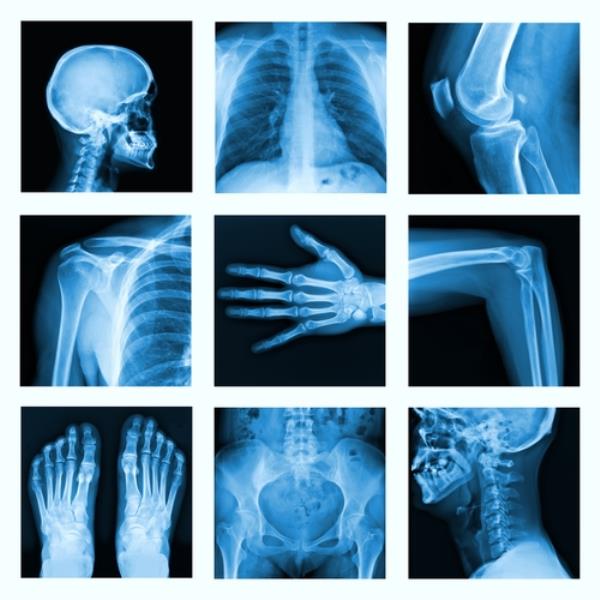

An X-ray of the painful part of the bone is usually able to identify a tumour, although sometimes it can be difficult to see. Other tests may be carried out to see whether the cancer has spread. Chemotherapy is given before and/or after the tumour is removed. Radiotherapy can be used to shrink a tumour if it is in a part of the body difficult to operate on, for example the pelvis. It may also be used after surgery to help lower the risk of recurrence.

Regular check-ups after treatment will include chest X~rays, because Ewing’s sarcoma can spread to the lungs. You will also have CT and MRI scans, but not at every visit.